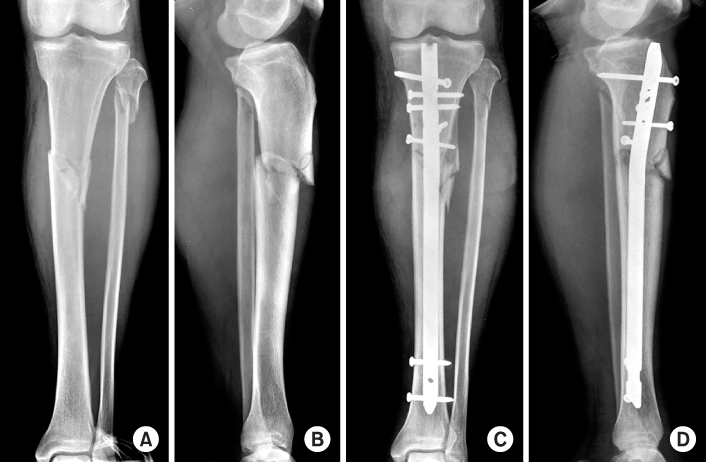

Fig. 1

Radiographs show a healed fracture of the proximal tibia with valgus deformity and apex anterior deformity after locked nail.

Fig. 1 Radiographs show a healed fracture of the proximal tibia with valgus deformity and apex anterior deformity after locked nail.